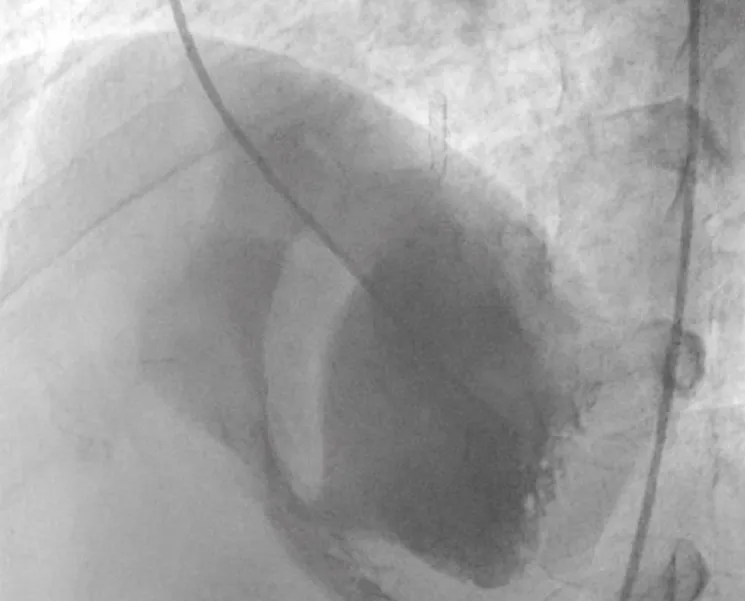

There was no use of transesophageal echocardiography due to the unavailability of a suitable probe. Left Ventricular angiogram was done to determine the exact location of the VSR (Figure 2). Cannulation of the right femoral artery and right internal jugular vein or right femoral vein was performed using the Seldinger technique. A guidewire (03500 Terumo guidewire) was introduced from the femoral artery, through the aorta into the left ventricle, and advanced through the VSR into the right ventricle and pulmonary artery. A second snaring wire was introduced through the vein (Either jugular or femoral) to connect to the guidewire in the pulmonary artery. By retracting the snared wires, the guidewire now forms an arteriovenous (AV) loop. The delivery sheath was advanced from the venous side loop over the guidewire through the VSR into the left ventricle. Correct positioning of the delivery sheath is confirmed in fluoroscopy/TTE. The guidewire is then retracted leaving the delivery sheath in position. After the echocardiographic confirmation occluder device was deployed across VSR using the delivery sheath (Figure 3). Correct positioning of the device and closure was confirmed by transthoracic echocardiography and/or fluoroscopy. If placement is satisfactory, the occluder is released. Post-procedure Left ventricular angiography and transthoracic echocardiography (Figure 4) were done to confirm the position and to rule out the presence of any residual shunt. We did not perform transoesophageal echocardiography for delineation of post-MI VSR, in any of the patients of our series due to the lack of availability of probes. In two cases we did not use any contrast agent (angiography) to delineate VSR because both patients had very high levels of urea and creatinine. Out of 11, in 10 cases, we made use of the femoral-jugular mode of access and created an AV loop. In one case we made a femoral arterio-venous loop. The veno-venous loop though described in literature was not used in this study.

Figure 2: Ventricular angiogram to determine the exact location of the VSR.